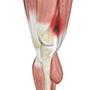

Muscles of the Knee

Muscles: There are two major muscles, the quadriceps and the hamstrings, which enable movement of the knee joint. The quadriceps muscles are in the front of the thigh. When the quadriceps muscles contract, the knee straightens. The hamstrings are in the back of the thigh. When the hamstring muscles contract, the knee bends.

Tendons of the Knee

Tendons are structures that attach muscles to the bone. The quadriceps muscles of the knee meet just above the patella and attach to it through a tendon called the quadriceps tendon. The patella further attaches to the tibia through a tendon called the patella tendon. The quadriceps muscle, quadriceps tendon and patellar tendon all work together to straighten the knee. Similarly, the hamstring muscles at the back of the leg are attached to the knee joint with the hamstring tendon.